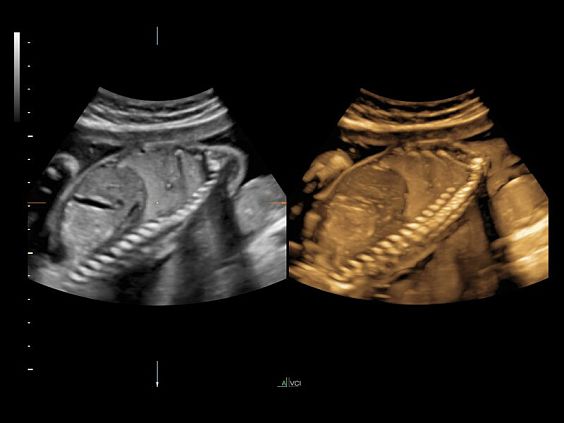

Клинические изображения

• Программа объемной визуализации плода классический HD-Live + расширенный пакет Hdlive Silhouette и Studio:

• HDlive Flow - перемещаемый источник света, совместимый с визуализацией кровотока в 3D

• HDlive Silhouette - режим "Силуэт" с подчеркиванием границ тканей и объектов, "объем в объеме"

• HDlive Flow Silhouette - режим "Силуэт" с выделением границ полостей сердца и сосудов, совместимый с визуализацией кровотока

• HDlive Studio - три независимых источника освещения с регулировкой интенсивности

• Автоматическое определение плода в режиме 3D (SonoRenderLive) – позволяет значительно экономить время и получать изображение конечностей и лица плода в режимах 3D без артефактов и помех – система автоматически определяет границы конечностей и лица плода и выстраивает объемное изображение

Объемное сканирование Voluson — 3D/4D вашей мечты

Объемное УЗИ на Voluson E10 — это не просто потрясающе красивая картинка, это ценный инструмент получения дополнительной информации при обследовании женщин.

Voluson E10 поддерживает инновационные технологии формирования изображений — HDlive Silhouette и HDlive Flow, которые позволяют увидеть мельчайшие детали. Алгоритм SonoRenderlive упрощает рабочий процесс и дает возможность реконструировать изображение поверхностей, определяя область перехода между тканью и жидкостью.

• HDlive

Инновационная технология визуализации HDlive обеспечивает получение реалистических изображений за счет эффекта объемного зрения, повышая достоверность клинической оценки. Теперь режим HDlive дополняют две новые функции:

• Технология HDlive Silhouette — задает разный уровень прозрачности, помогая выявлять контуры внутренних структур и точнее оценивать состояние плода в первом триместре.

• Технология HDlive Flow — повышает реалистичность визуализации сосудистых структур, улучшая восприятие глубины (по сравнению с традиционным цветовым допплером и функцией HD-Flow).